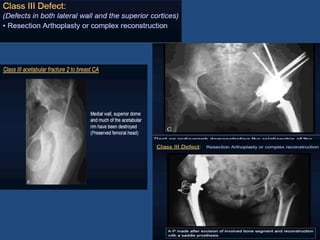

Pelvic Discontinuity

• Disruption of Anterior &

Posterior columns.

• No bony continuity between

illium and ischium/pubis

• Non-Supportive Superior

dome with >3cm migration

Pelvic Discontinuity • Disruptionof Anterior & Posterior columns. • No bony continuity between illium and ischium/pubis • Non-Supportive Superior dome with >3cm migration